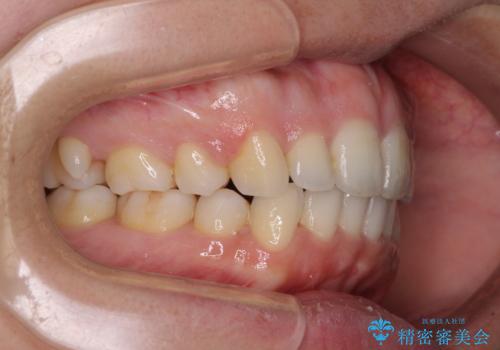

- 前歯のデコボコと口元の突出感を気にして来院された患者様です。

上下左右第一小臼歯4本を抜歯し、ワイヤー装置にて口元を引っ込めるよう矯正治療を行うこととしました。

叢生が強かったため、口元の突出感の改善には限界がありましたが、横側からも口元が引っ込んだ感じが分かるほど改善されました。